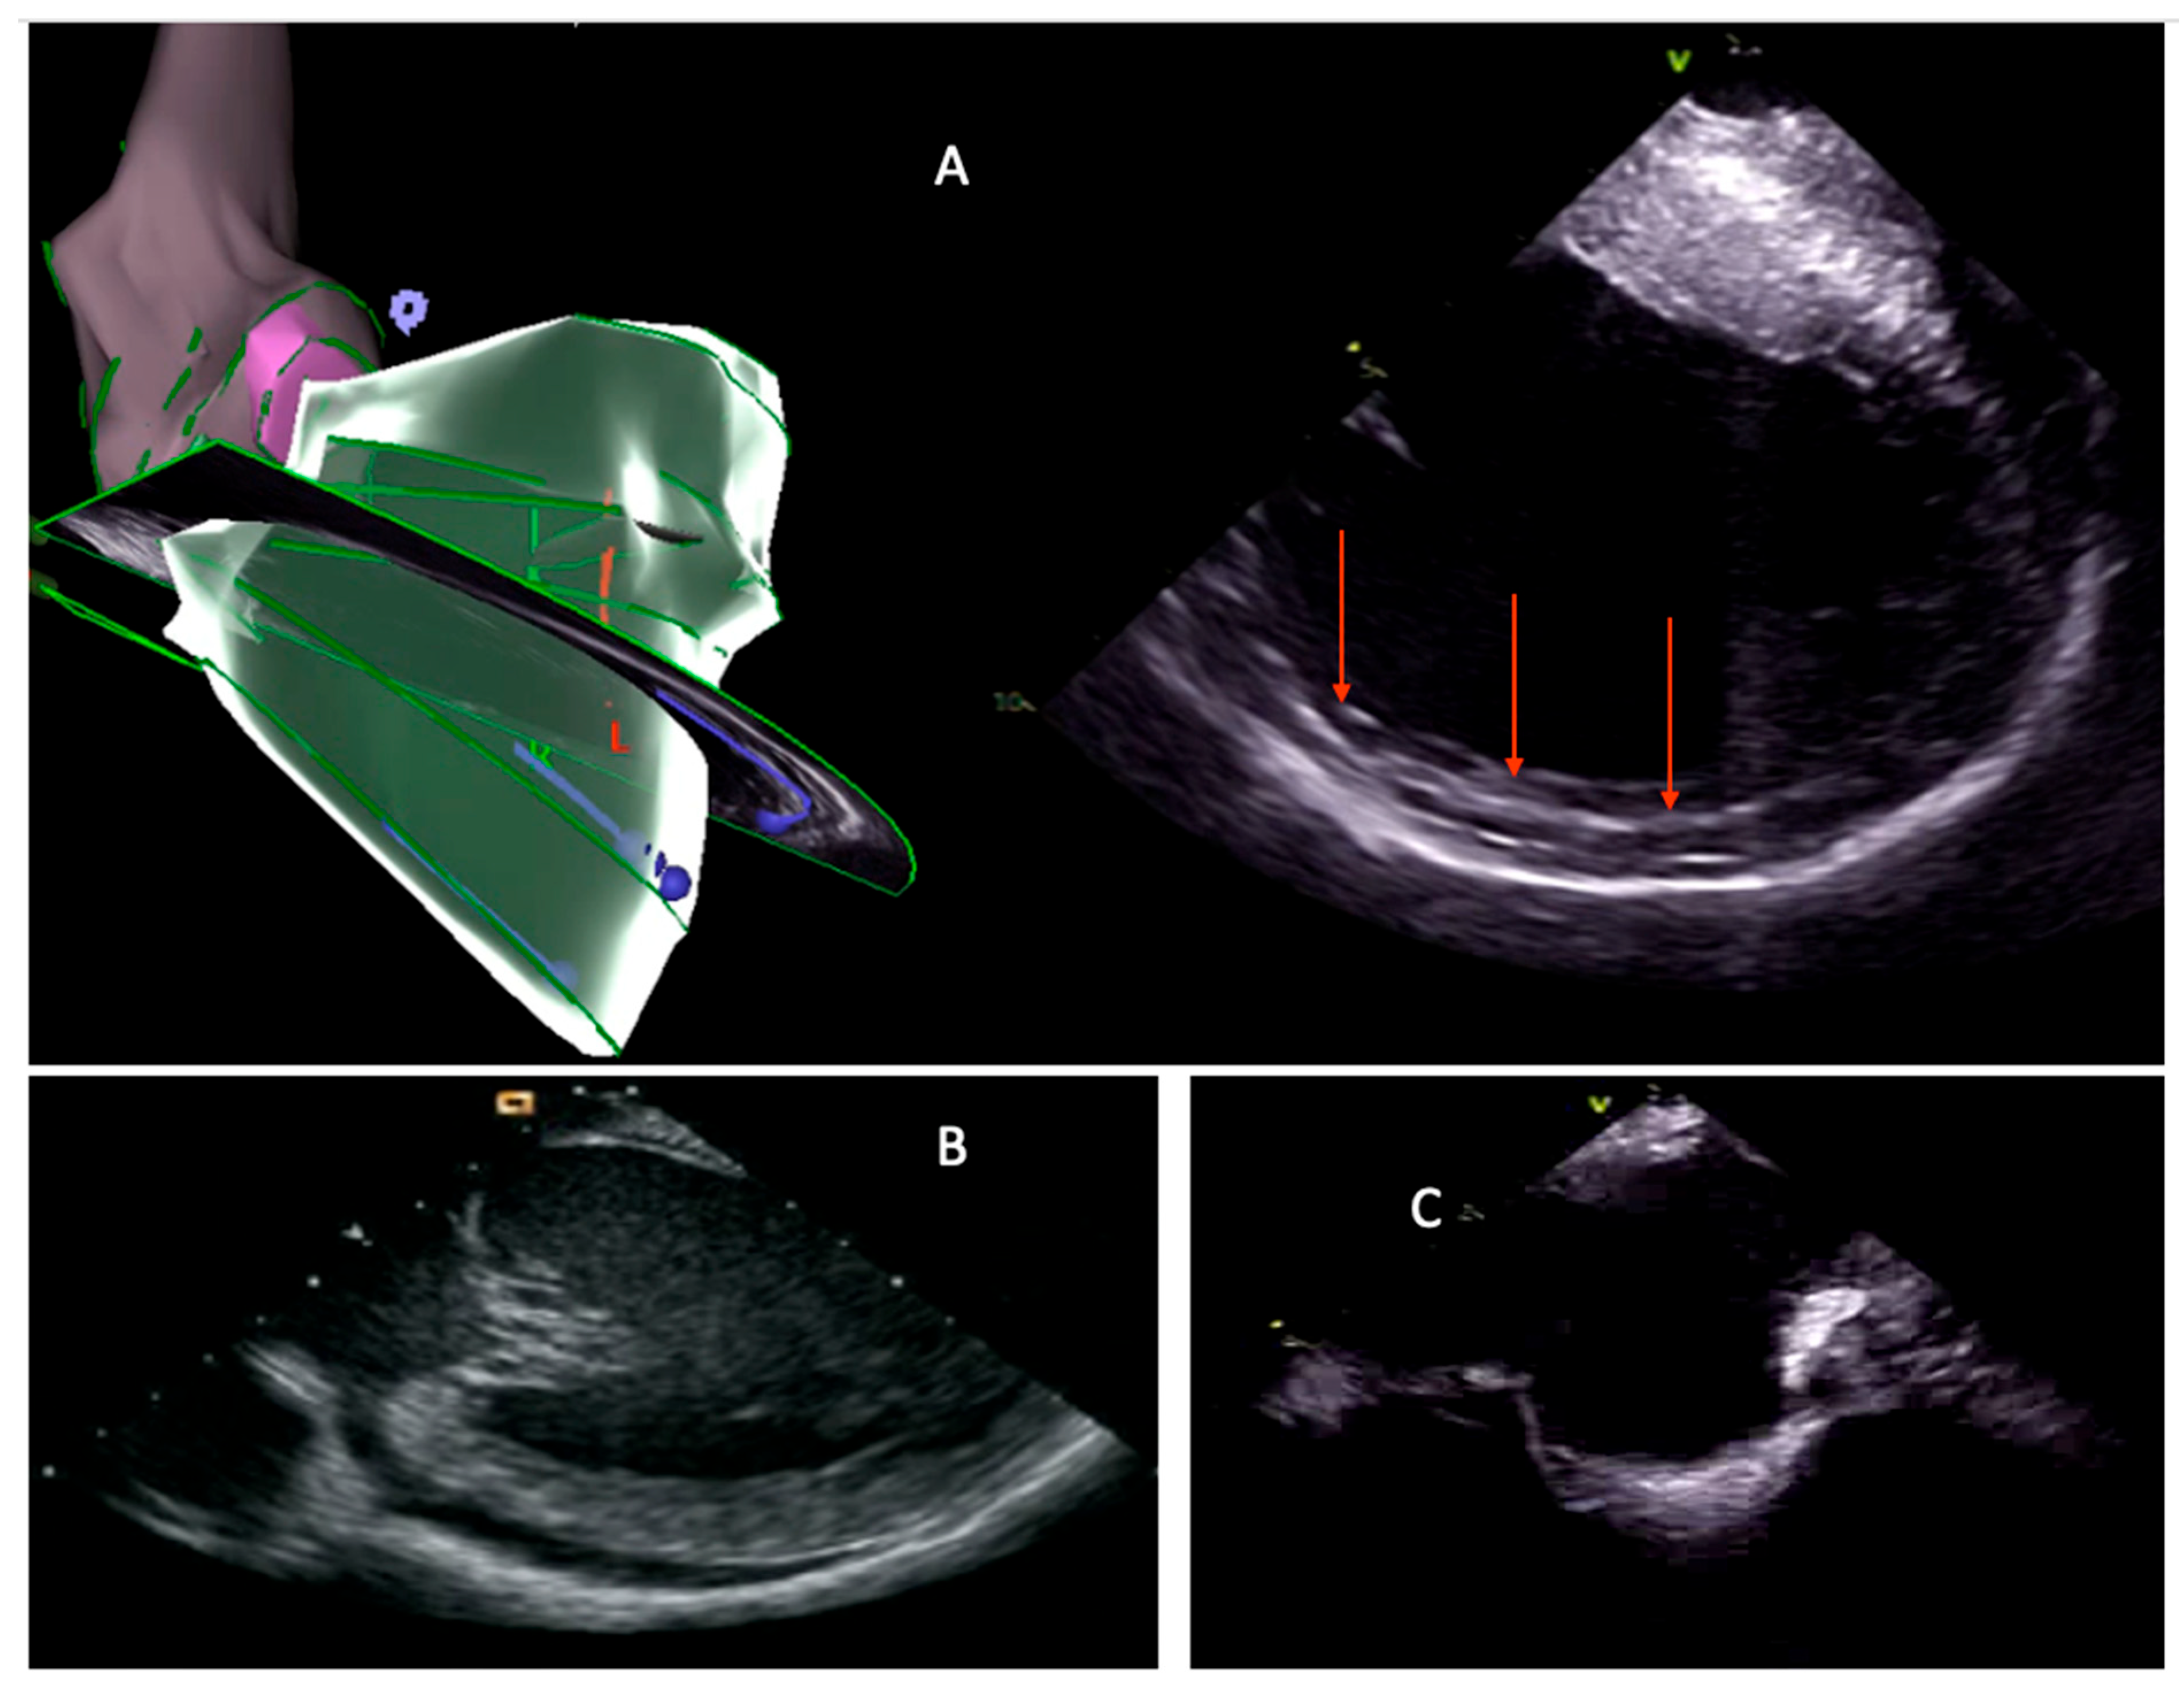

3. Intraprocedural Imaging: Focus on Intracardiac Echocardiography

3.1. Anatomical Delineation and Catheter Navigation

3.2. Substrate Characterization